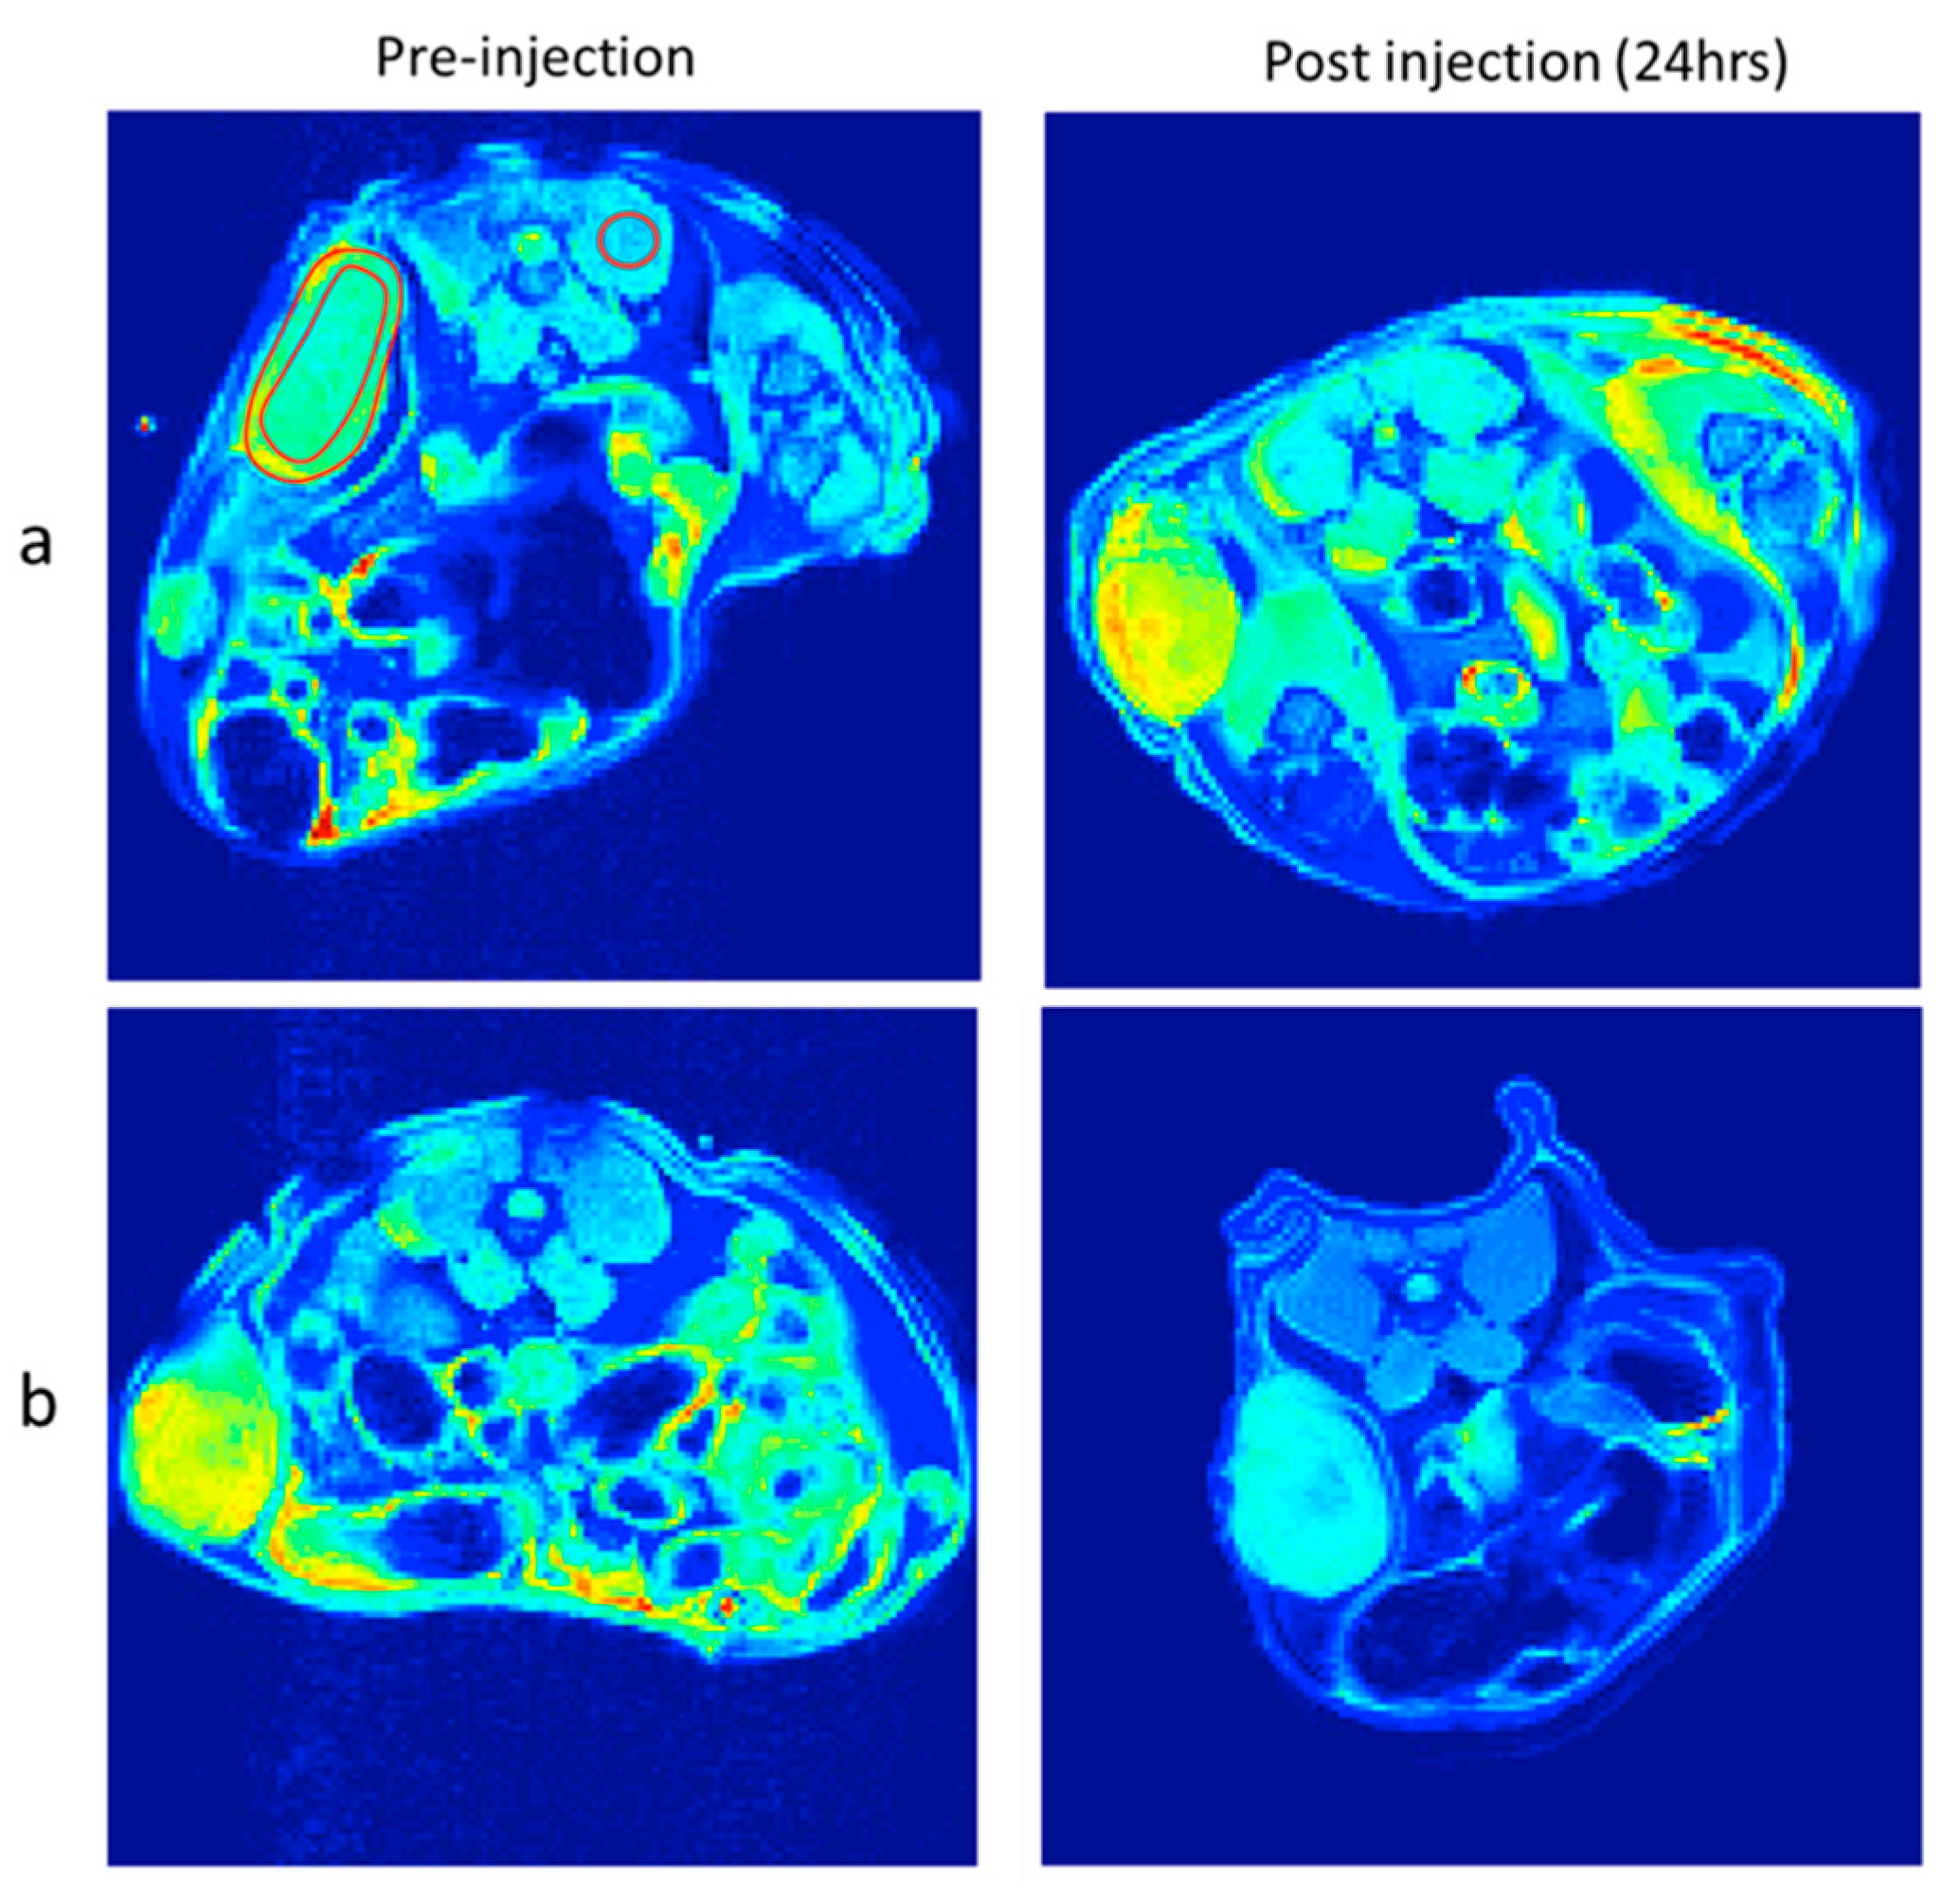

3.5.3. In Vivo T2 Weighted Images

| Position | F127 Coated SPION | F127-Folate Coated SPION | ||||

|---|---|---|---|---|---|---|

| Pre-Injection | Post-Injection | Reduced Signal (%) | Pre-Injection | Post-Injection | Reduced Signal (%) | |

| Tumor rim/back muscle | 1.5 | 1.5 | 99.8 | 1.6 | 1.4 | 85.6 |

| Tumor core/back muscle | 1.3 | 1.5 | 117.7 | 1.8 | 1.4 | 80.3 |

| Whole tumor/back muscle | 1.3 | 1.4 | 108.1 | 1.7 | 1.4 | 83.2 |